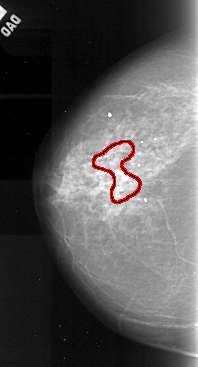

A_1049_1.LEFT_MLO

FILE: A_1049_1.LEFT_MLO.OVERLAY

TOTAL_ABNORMALITIES 1

ABNORMALITY 1

LESION_TYPE CALCIFICATION TYPE PLEOMORPHIC DISTRIBUTION SEGMENTAL

ASSESSMENT 4

SUBTLETY 3

PATHOLOGY MALIGNANT

TOTAL_OUTLINES 1

BOUNDARY